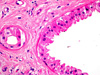

CASO N° 2 (Dr. Elismauro e Dr. Delgado)

Paciente do gênero masculino, 85 anos de idade, apresenta um aumento de volume na maxila esquerda.